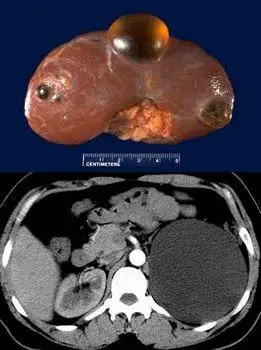

隐性遗传性多囊肾的切面.囊肿相当小,但广泛分布于实质.